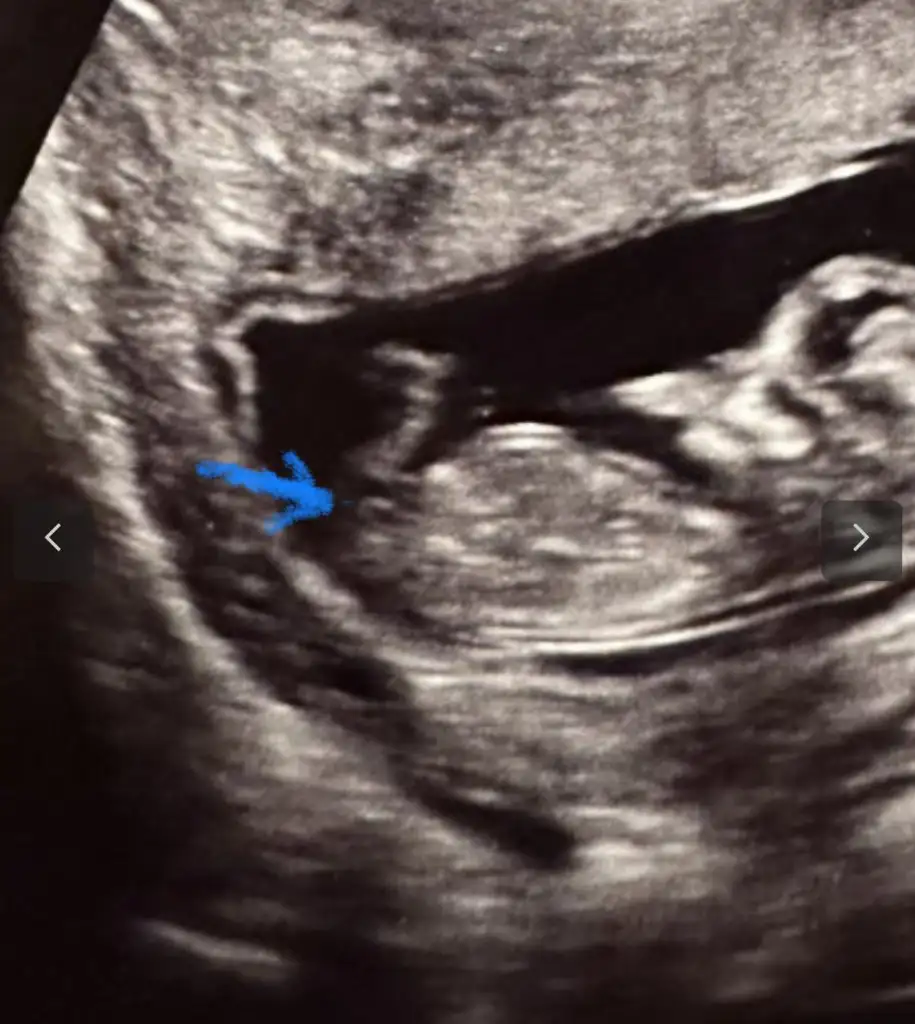

Suradaki cıkıntıdan gördümevet doktorumuzda aynı tahminde bulundu nasıl bilebiliyorsunuz

Kesenin şekli cnmevet doktorumuzda aynı tahminde bulundu nasıl bilebiliyorsunuz

sizceeeee cinsiyetimiz nedirErkek bence cnm

sizceeeee cinsiyetimiz nedir